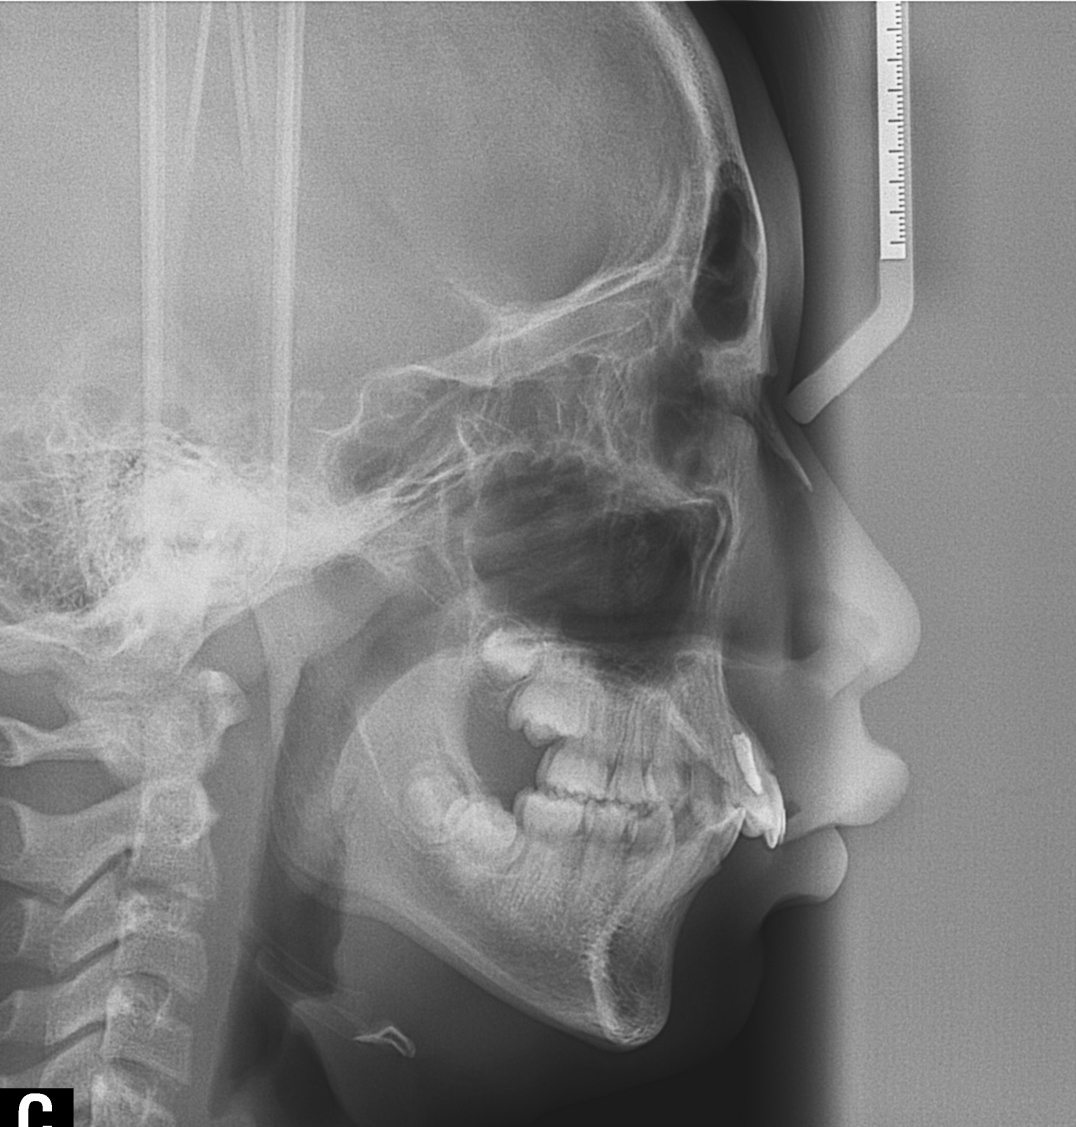

À§ ȯÀÚ´Â À´Ï°¡ ¾Æ·§´Ï¸¦ ³Ê¹« µ¤¾î¿ä(°ú°³±³ÇÕ) ¸¦ ÁÖ¼Ò·Î ³»¿øÇÑ ÃʵîÇлýÀ̾ú½À´Ï´Ù. ÅμºÀå ¾ÇÁ¤ÇüÀåÄ¡ »ç¿ëÈÄ È£ÈíÀÌ °³¼± µÇ¾úÀ¸¸ç Ä¡·áÀü¿¡ ºñÇØ ۰¡ 10cmÁ¤µµ ±Þ¼Ó ¼ºÀåÇÏ¿´½À´Ï´Ù.

°ú°³±³ÇÕ°ú ¹«ÅÎ,ÅΰüÀýÀ» ÁÖ¼Ò·Î ³»¿øÇÏ¿© ÅμºÀå ¾ÇÁ¤ÇüÀåÄ¡¸¦ ÀÌ¿ëÇÏ¿© Ä¡·áÁßÀΠȯÀÚ·Î Ä¡·á½ÃÀÛ½ÃÁ¡ ±âÁØÀ¸·Î ÇöÀç ۰¡ ¾à 8cmÁ¤µµ ¼ºÀåÇÏ¿´½À´Ï´Ù. (Âü°í·Î 2³âÂ÷ ¿©µ¿»ý°ú ۰¡ 7-9cmŰ Â÷À̳²)